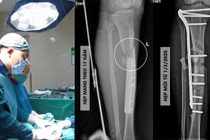

Trong tháng 6/2025, Khoa Chấn thương – Bỏng, Bệnh viện Đa khoa tỉnh Lạng Sơn đã tiếp nhận hơn 50 trường hợp trẻ em bị tai nạn thương tích, trong đó phần lớn là chấn thương gãy trên lồi cầu xương cánh tay, tăng khoảng 15% so với cùng kỳ năm 2024.

Các bệnh nhi nhập viện với cảm giác vô cùng đau đớn, vận động gặp nhiều hạn chế và đều phải can thiệp phẫu thuật đồng thời trải qua thời gian dài để phục hồi chức năng. Phần lớn các tai nạn của trẻ xảy ra tại nhà hoặc trong sinh hoạt, thường do trẻ chạy nhảy, ngã chống tay gây chấn thương.

Thăm khám cho trẻ bị gãy lồi cầu xương cánh tay - Ảnh BVCC

BSCKII Nguyễn Văn Nam, Khoa Khám xương và Điều trị ngoại trú, Bệnh viện Hữu nghị Việt Đức cho biết, gãy trên lồi cầu xương cánh tay trẻ em là loại gãy xương vùng khuỷu tay thường gặp nhất ở trẻ em.

Gãy trên lồi cầu xương cánh tay trẻ em là kiểu gãy xương ngoại khớp, ở vùng hàng xương của đầu dưới xương cánh tay, đường gãy nằm trên lồi cầu và ròng rọc, đi ngang hố khuỷu.

Điều trị gãy trên lồi cầu trẻ em thì điều trị bảo tồn bằng nắn chỉnh, bó bột theo giai đoạn được ưu tiên hàng đầu.